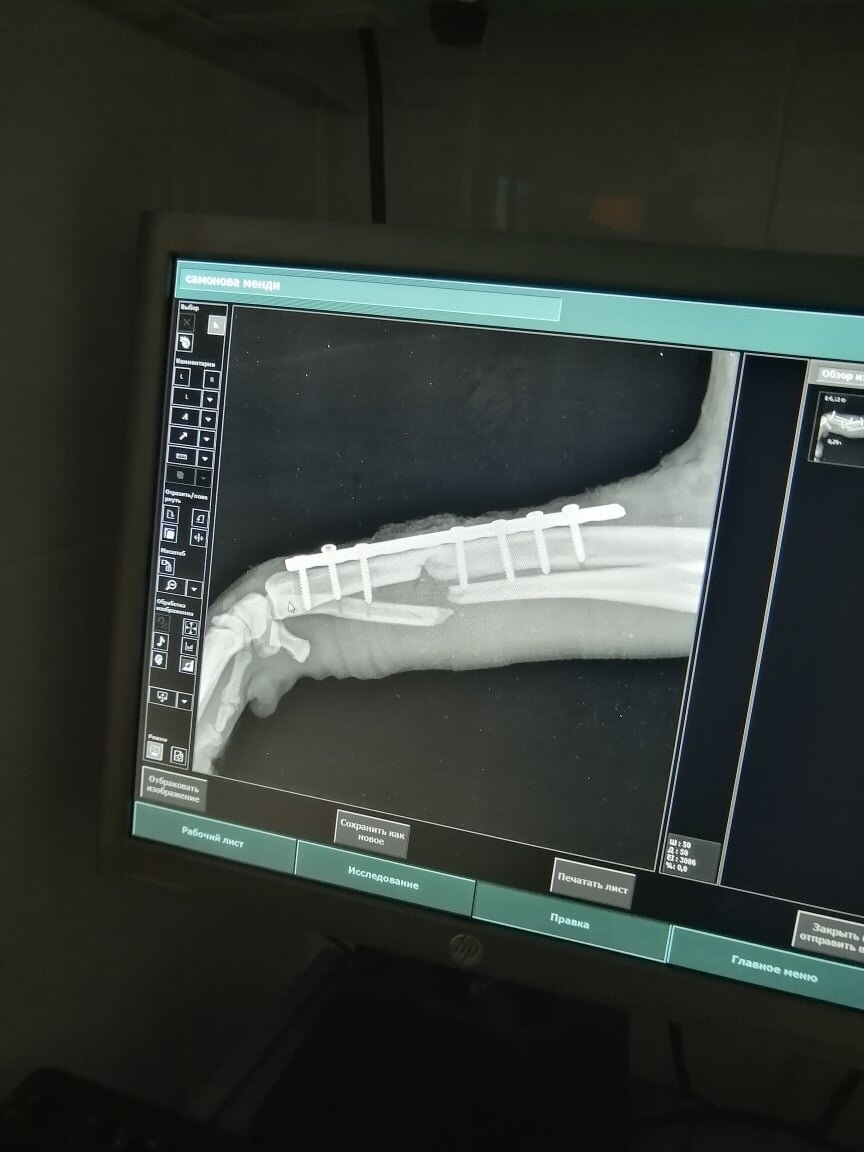

Женщина, которая её подкармливала, связалась со мной и попросила свозить собаку в клинику, так как у неё была травмирована лапа. Рентген в клинике показал перелом двух костей передней лапы, что, скорее всего, явялеется результатом ДТП. Через несколько дней повезли её на операцию в Никольский, где ей поставили пластину. Одну из костей так и не получилось соединить, но опора при ходьбе будет именно

Женщина, которая её подкармливала, связалась со мной и попросила свозить собаку в клинику, так как у неё была травмирована лапа. Рентген в клинике показал перелом двух костей передней лапы, что, скорее всего, явялеется результатом ДТП. Через несколько дней повезли её на операцию в Никольский, где ей поставили пластину. Одну из костей так и не получилось соединить, но опора при ходьбе будет именно на ту кость, на которую поставили пластину. Менди пока не встаёт на лапу, хотя активно бегает на трёх. Уже повторно делали рентген и получили новый курс лечения от врача. Надо ждать, надо принимать лекарства и смотреть, как будет дальше.